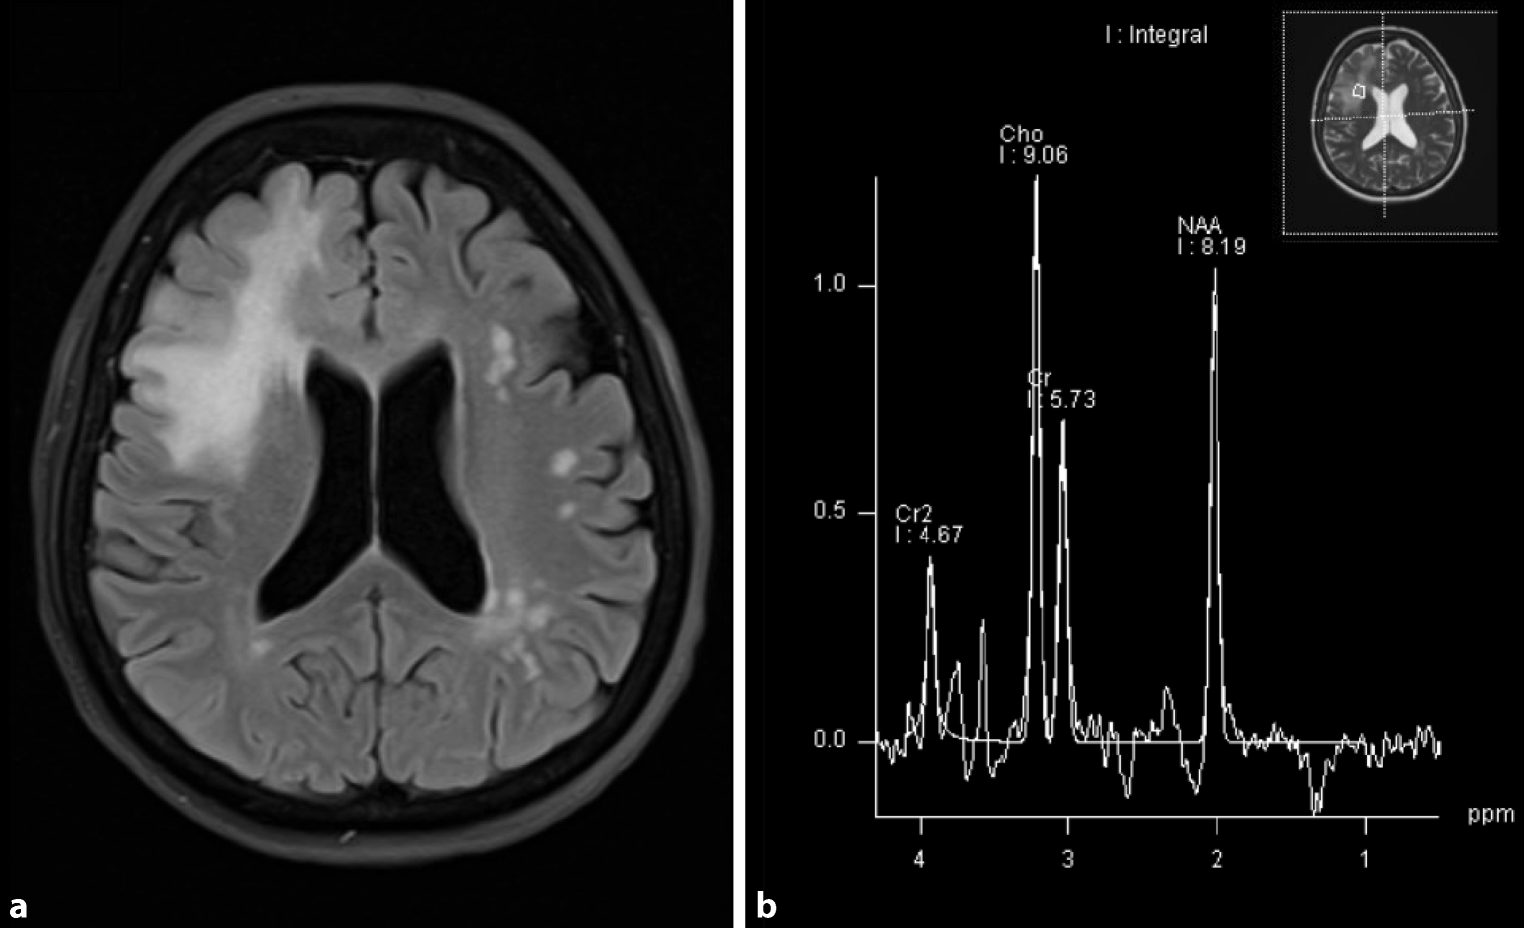

Due to recurrent episodes with headaches, external cerebral MRI scans had been performed in 2002 and 2008 and shown unspecific white matter lesions. Until 2019, no other neurological symptoms or relapses were reported, and the patient received no other immunomodulatory treatments than colchicine. After the occurrence of new cognitive symptoms, a follow-up MRI scan in October 2019 showed a new, ill-defined white matter lesion in the right frontal lobe, with mild local mass effect but without contrast enhancement. In the cerebral MRI from December 2020, the lesion was essentially constant in size and appearance (Fig. 1a). The additional MR spectroscopy showed markedly increased choline levels accompanied by a lactate peak, highly suggestive for a low-florid demyelinating process (Fig. 1b). Due to the lesion size > 2 cm, the slight mass effect, and the demyelinating character, we classified the right-sided frontal lobe lesion as a tumefactive demyelinating lesion [4]. Further diagnostic procedures including brain biopsy or FET-PET were discussed with the patient but not pursued, also following the patient’s choice.

Fig. 1

Tumefactive, demyelinating central nervous system lesion in MRI and MR spectroscopy transverse fluid-attenuated inversion recovery (FLAIR) image. Image (a) shows extensive T2 hyperintensity of the right frontal lobe with a maximum range of 6.2 cm. No associated contrast enhancement or diffusion restriction could be detected (disease exacerbation > 12 months before current MRI). Image (b) shows MR spectroscopy using chemical shift imaging with an increase of choline (Cho), normal N‑acetyl aspartate (NAA), and a characteristic negative double peak at 1.3 ppm, representing lactate. The marked increase of choline accompanied by the lactate peak is highly suggestive of a low-florid demyelinating process

A number of case reports [5, 6] have already described demyelinating CNS lesions and the diagnosis of multiple sclerosis (MS) in association with FMF and MEFV mutations [1, 7, 8]. In our patient, the diagnostic criteria for MS were not fulfilled due to the lack of defined clinical relapses. Furthermore, typical CSF features, such as CSF-specific OCBs, were not detectable. As possible differential diagnoses for the tumefactive lesion, infectious diseases as well as a brain tumor appeared to be unlikely due to the stable presentation over 1 year and the MR spectroscopy results which showed a marked increase of choline, no relevant reduction of the N‑acetyl aspartate peak, and a significant lactate peak, suggestive for a demyelinating process. Consequently, the described lesions including the tumefactive lesion were classified as demyelinating lesions in the context of the FMF diagnosis and treatment was changed to an anti-IL‑1 therapy (anakinra). As a limitation of this case, it has to be pointed out that there is no final evidence causally linking the tumefactive lesion to FMF. In follow-up, clinical symptoms and MRI remained stable, with a slight improvement of cognitive deficits. Although the exact pathophysiology underlying CNS lesion formation in FMF remains unclear, the increased activity of IL-1β has been suggested to facilitate a proinflammatory milieu that triggers endothelial dysfunction and favors the development of autoreactive lymphocytes [7].